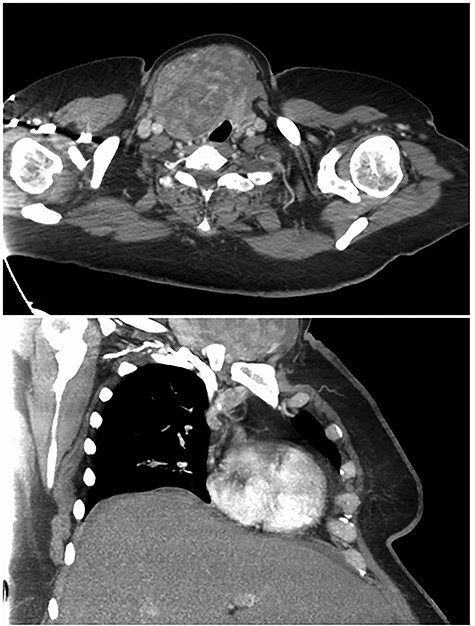

A 48-year-old morbidly obese woman with a history of metastatic endometrial carcinoma who was status post-total abdominal hysterectomy and bilateral salpingo-oophorectomy presented for evaluation of a large right-sided goiter found incidentally on computed tomography (CT) performed as part of her metastatic cancer evaluation. CT revealed a 10 cm right thyroid mass with extension deep to the right clavicle and associated tracheal compression (Fig. 1). Positron emission tomography revealed no evidence of metastatic disease but displayed diffuse thyroid hypermetabolism.

Preoperative computed tomography images highlighting large right thyroid nodule with tracheal compression.